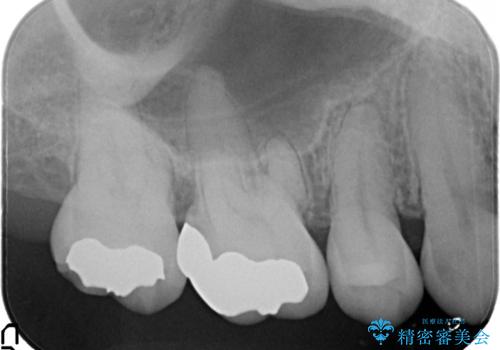

むし歯の治療。ゴールドインレーによる修復

- 定期健診にてむし歯を認めたためゴールドインレーにて治療を行いました。

拡大鏡で常に口腔内を診察しているため、小さなむし歯も見逃さずに治療を行っています。